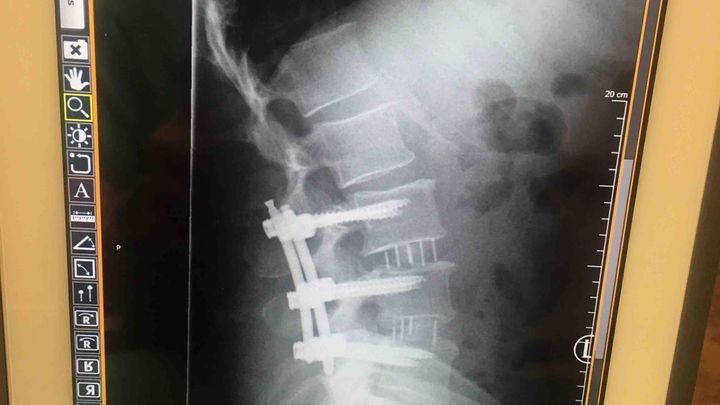

I went to the ER they performed an MRI and said I have 1 bulging disk another disk I smashed that is leaking fluid and on my sciatic nerve causing extreme pain in my right leg and hip. Went to the neurosurgeon and I have no other choice but surgery to take most or all of the pain away. And to be able to interact with my children And go back to work.

I had back surgery. Will be out of work for 4to5 months.